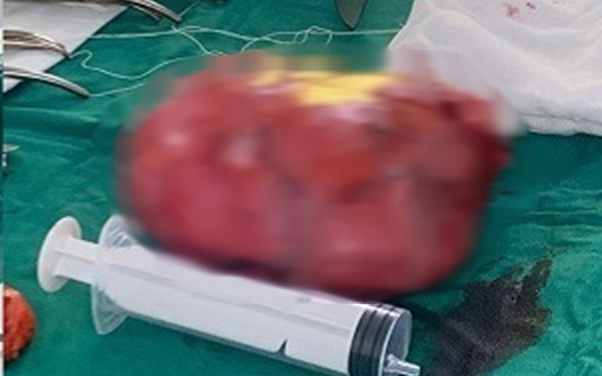

Hạt hồng xiêm được lấy ra khỏi đường thở bệnh nhi. Ảnh: BVCC.

Tại Trung tâm Hô hấp, bệnh nhi được chỉ định nội soi phế quản để gắp dị vật. Quá trình can thiệp gặp nhiều khó khăn do dị vật đã tồn tại lâu ngày, bị bao bọc bởi tổ chức viêm và mô hạt. Các bác sĩ phải phối hợp nội soi ống cứng với laser để cắt bỏ tổ chức xung quanh và lấy ra dị vật là hạt hồng xiêm kích thước khoảng 1×3cm.